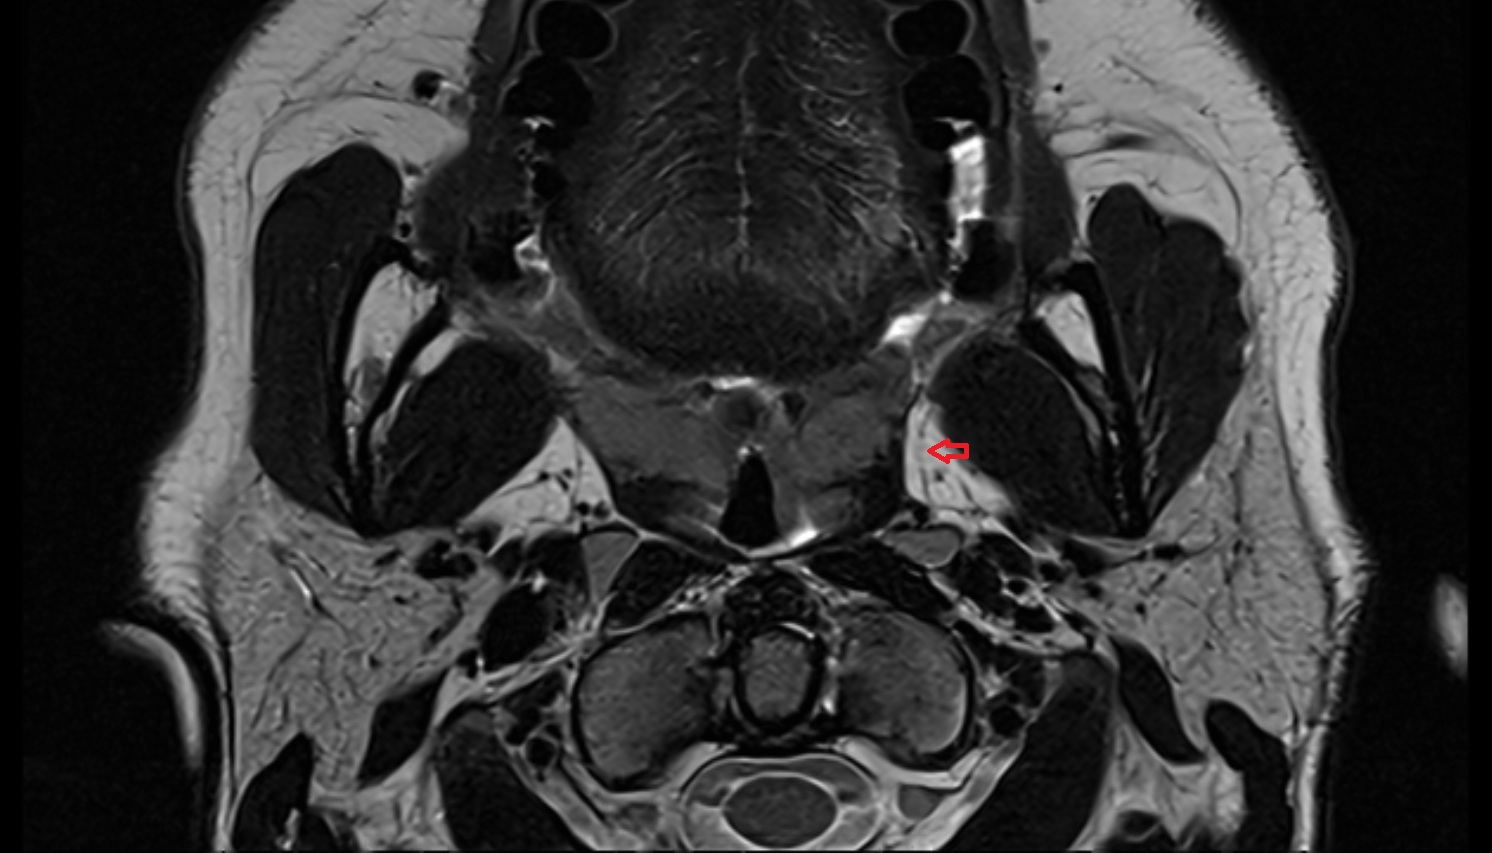

- Peripheral zone of prostate

- Anterior Fibromuscular Stroma of prostate

- Central zone of prostate

- Transitional zone of prostate